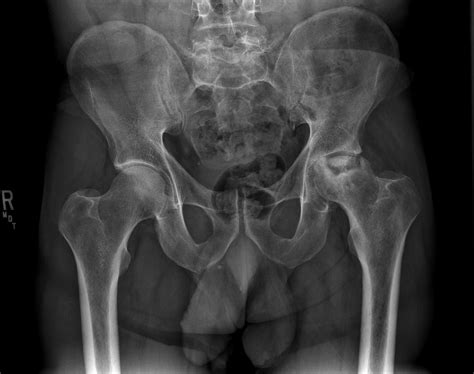

Clinicians typically categorize Avn disease hip into four distinct stages based on imaging techniques like MRI and X-rays. Identifying the stage is paramount because treatment options vary drastically depending on how much of the femoral head is affected.

Stage II Sclerosis or osteopenia visible on X-ray. Increased pain with weight-bearing activities.

Stage III The "crescent sign" appears, indicating subchondral collapse. Constant ache, limited range of motion.

Stage IV Degenerative changes and joint surface destruction. Severe pain and significant mobility loss.